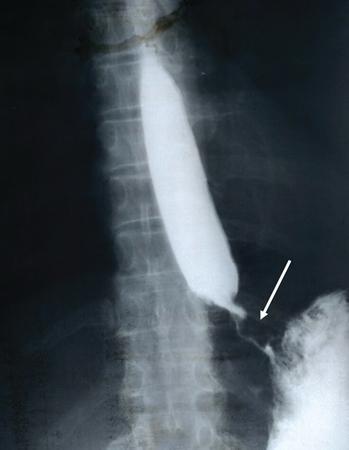

Fifty-year-old male with history of progressive dysphagia of one-year duration.

Upright oblique anteroposterior image reveals a markedly dilated barium-lined oesophagus showing food residue, mottled gas and an air-fluid level. The dilated oesophagus shows smooth distal tapering to a ‘bird beak’-like appearance below the diaphragm (arrow). On fluoroscopy, primary oesophageal peristalsis was absent.

Principal Diagnosis: Achalasia cardia.

Differential diagnosis

1. 1. Presbyoesophagus

2. 2. Carcinoma

3. 3. Scleroderma

4. 4. Oesophagitis with stricture